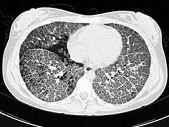

- 单项选择题女,18岁, 呼吸困难,消瘦, 糖原PAS染色阳性,结合图像, 最可能的诊断是 ( )

E、肺泡蛋白沉积症